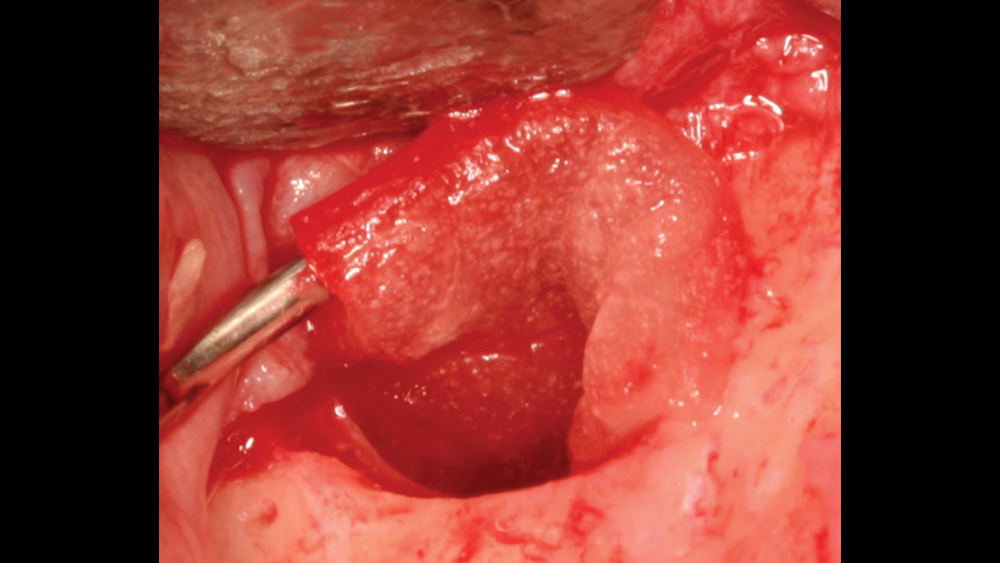

Platelet-Rich Fibrin

The use of platelet-rich fibrin (PRF) is increasing in popularity for GBR procedures (Figs. 10a–10d). This second-generation platelet concentrate has the advantages of lower cost, no need for additional reactive agents, and a higher concentration of platelets in comparison to platelet-rich plasma. The PRF protocol involves the centrifuging of the patient’s whole blood, resulting in the formation of three layers. The bottom layer contains red blood cells, which is discarded; the top layer is clear-colored and is termed platelet-poor plasma; and the middle layer, which is the fibrin matrix, is used as a membrane in bone regeneration procedures.

Figure 10a Platelet-rich fibrin

Figure 10b Platelet-rich fibrin

Figure 10c Platelet-rich fibrin

Figure 10d PRF membrane is placed

Figures 10a–10d: Platelet-rich fibrin has the advantages of lower cost, no need for additional reactive agents, and a higher concentration of platelets in comparison to platelet-rich plasma. Shown, a venipuncture was performed to obtain approximately 10 cc of blood (10a). The platelet-rich fibrin is obtained (10b), followed by modification of the fibrin clot into the membrane (10c), and then the PRF membrane is placed (10d).